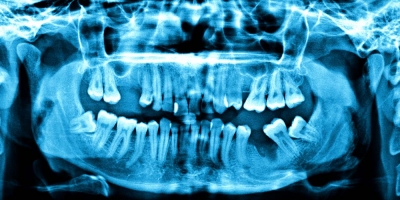

Dental X-Rays Double Your Chances of a Brain Tumor

Dental X-Rays Double Your Chances of a Brain Tumor You’re in the dentist chair to get your teeth cleaned and sooner or later your hygienist or dentist is likely to say, “It’s time for your annual X-rays.” Here’s why you should just say “no.” For years, dentists and the American Dental Association (ADA) have told [...]